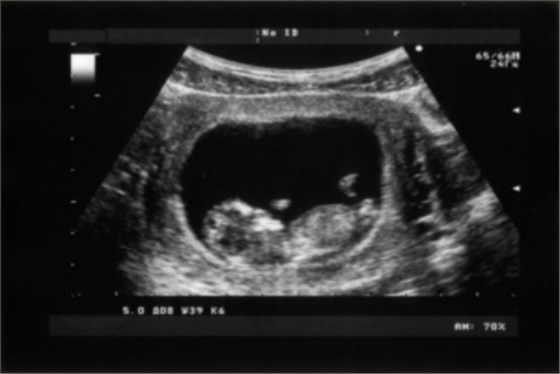

3、應用范圍:放射科可以進行全身的多部位的檢查,如頭部、頸部血管、心臟血管、甲狀腺、乳腺、縱隔、腹部臟器等多個部位的檢查,尤其是對占位性病變的檢查具有重要的臨床意義。超聲科可以進行小器官及臟器的檢查,如甲狀腺和乳腺、血管的檢查,心臟和各個瓣膜的檢查,以及肌肉和骨骼的檢查等;